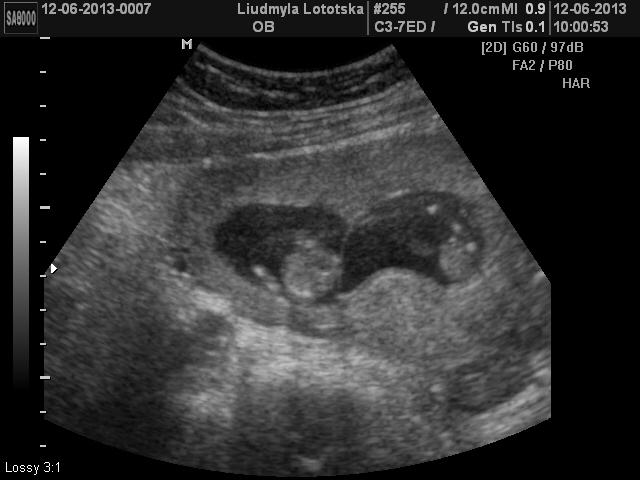

У меня ди-ди. Четко видно два яйца, у вас как-то больше на моно смахивает :) Кинула скан, для наглядности.

13.06.2013